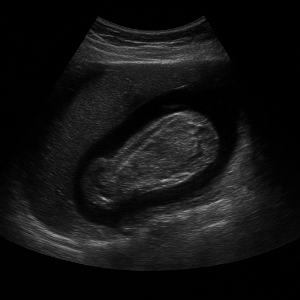

신장은 결석, 수신증(소변이 막혀 고여서 생긴 변화), 낭종, 종양 등의 상태를 초음파로 볼 수 있어요. 부신은 위치가 작고 깊지만, 우연종 같은 병변이 의심될 때 관찰할 수 있답니다.

신장 결석, 신부전, 낭종

- 신장 결석

콩팥에 생긴 작은 돌들은 초음파에서 반짝이며 그림자를 동반해 쉽게 보일 수 있어요. - 신부전 (수신증 등)

소변이 막혀서 신장이 붓는 상태를 ‘수신증’이라고 하는데요, 초음파로 신장의 부종이나 이상을 확인할 수 있어요. - 신장 낭종이나 종양

주머니처럼 생긴 낭종이나 덩어리가 있으면 초음파로 확인 가능해요.